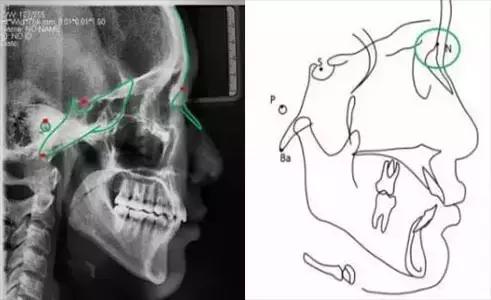

标志点是用来构成一些平面及测量内容的点。理想的标志点应该是易于定位的解剖标志,在生长发育过程中应相对稳定。但并不是常用的标志点均能符合这一要求,不少标志点的确定是由各学者提出的不同测量方法而定,而标志点的可靠性还取决于头颅X线片的质量以及描图者的经验。

头影测量标志点可分为两类:一类是解剖的,这一类标志点是真正代表颅骨的一些解剖结构;另一类是引伸的,这一类标志点是通过头影图上解剖标志点的引伸而得,如两个测量平面相交的一个标志点。

蝶鞍点(S.sella):蝶鞍影像的中心。这是常用的一个颅部标志点,在头颅侧位片上较容易确定。

鼻根点(N.nasion):鼻额缝的最前点。这是前颅部的标志点,代表面部与颅部的结合处。有些X线片上,此点显示不太清楚,是因为其形态不规则骨缝形成角度之故。

耳点(P.porion):外耳道之最上点。头影测量上常以定位仪耳塞影像之最上点为代表,称为机械耳点。但也有少数学者使用外耳道影像之最上点来代表,则为解剖耳点。

颅底点(Ba.basion):枕骨大孔前缘之中点。一般此点较易确定,常作为后颅底的标志。

这些标志点中,有些是在正中矢状面上,是单个的点。如鼻根点、蝶鞍点等。而有些则是双侧的点,如下颌角点,关节点等。若由于面部不对称而使两侧之点不重叠时,则取二点间的中点作为校正的位置。